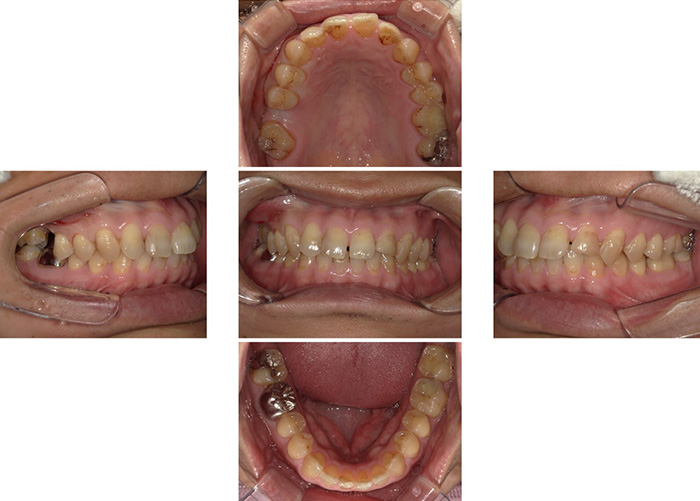

Case.02

![]() |

|---|

| 主訴 | 歯を抜いたので歯を入れたい |

|---|---|

| 治療期間 | 6か月 |

| 治療費 | 990,000円(税込1,089,000円) |

| 治療内容 | 右下の奥歯に2本インプラントを入れて、 3歯分の被せ物(ジルコニアベーシックブリッジ)を被せます。 |

| 治療のリスク | インプラント周囲炎になることがあります。 両隣の歯が将来抜歯になった場合、ブリッジの治療が選択できません。 |